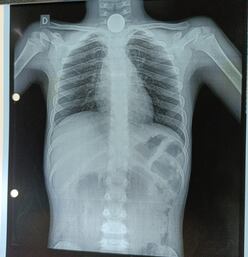

Radiografía al niño en el que se observa la moneda entre la garganta y el esófago. (gentileza).